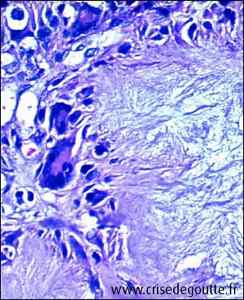

Microcristaux d'urate monosodique |

La goutte est un rhumatisme inflammatoire. Elle est due à la présence de microcristaux d’un sel de l’acide urique, l’urate monosodique, dans une articulati

on, ce qui entraîne l’inflammation de cette dernière. Il en résulte une réaction caractéristique très douloureuse. C’est la goutte aiguë, plus souvent appelée "crise de goutte" ou "accès goutteux." Ces crises vont guérir, mais peuvent récidiver, dans des délais variables et l'on parle alors de goutte chronique.